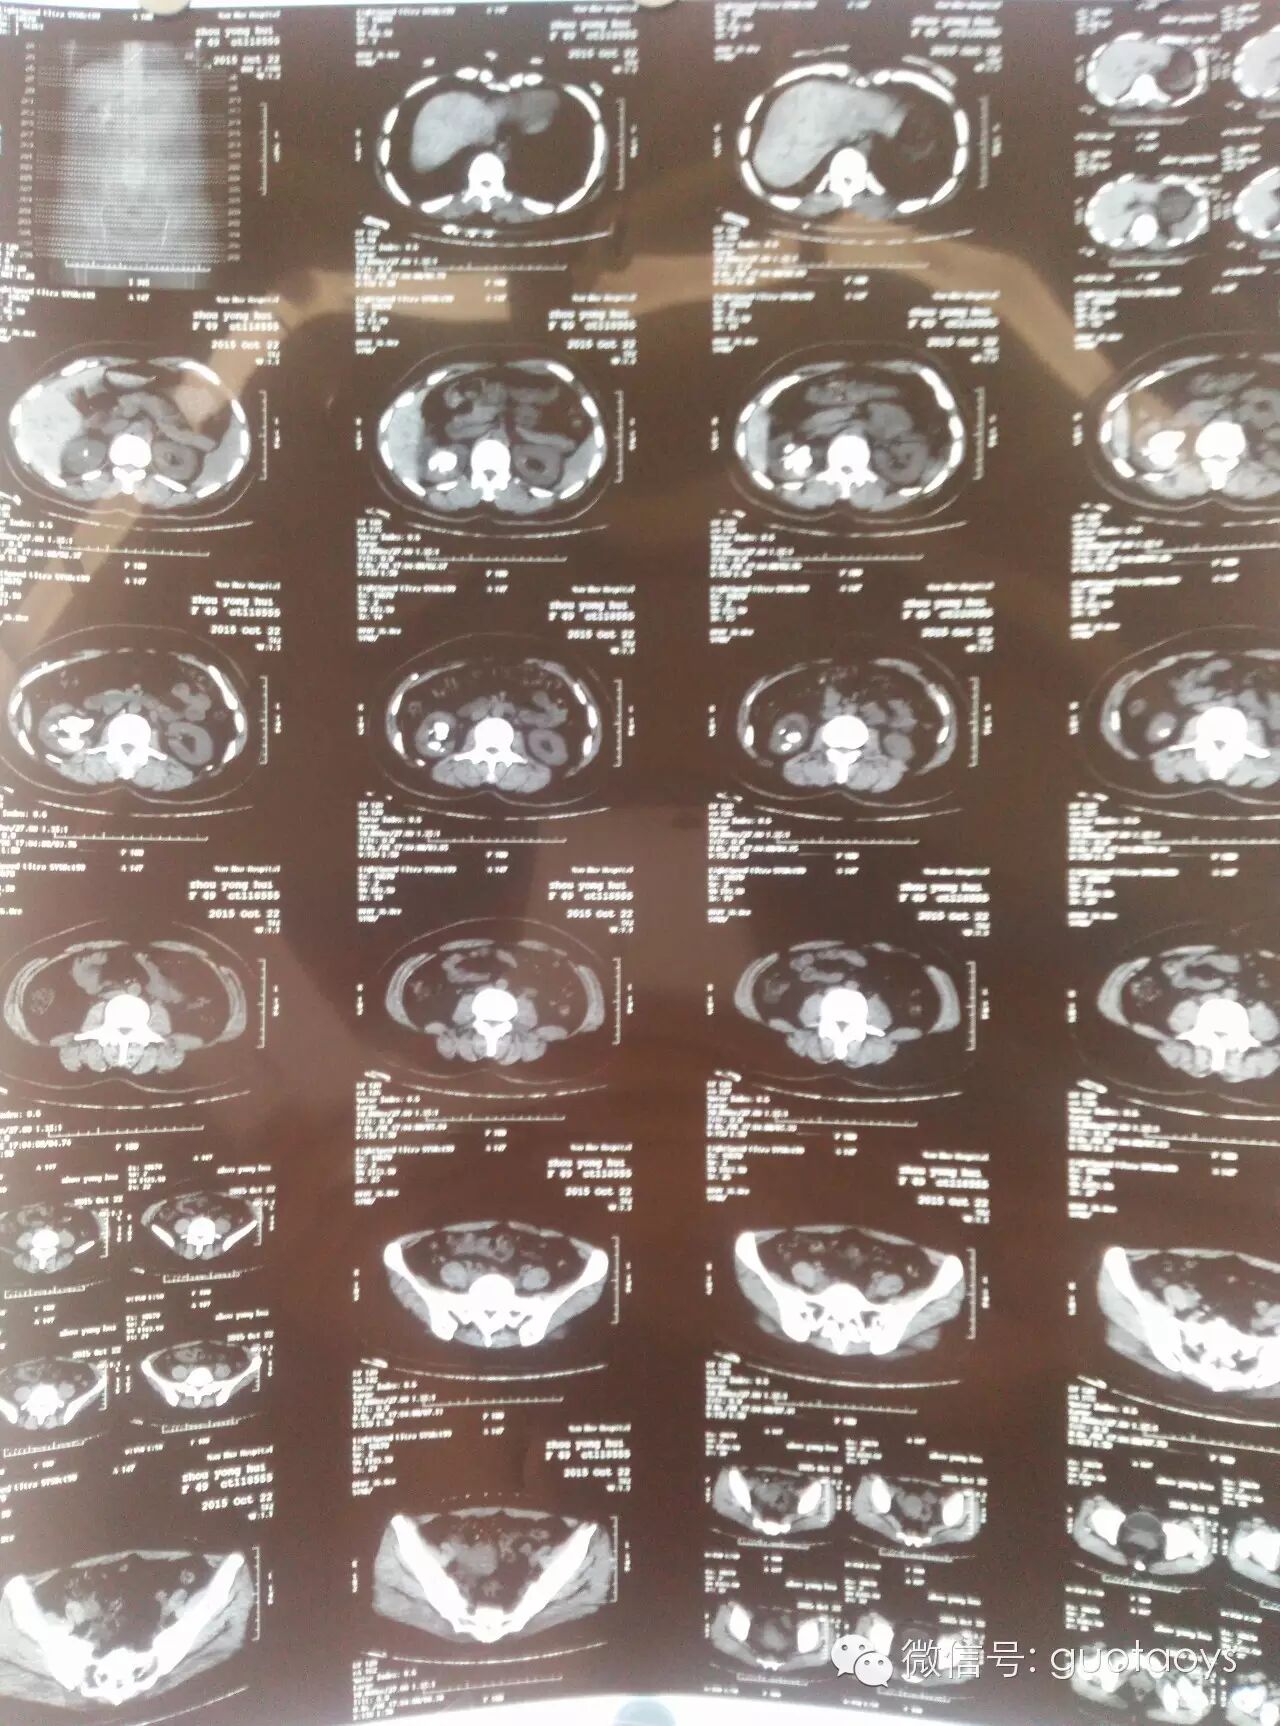

术前CT